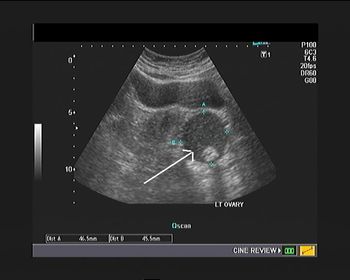

What is your diagnosis in this 7-year-old girl who presented with left pelvic pain?